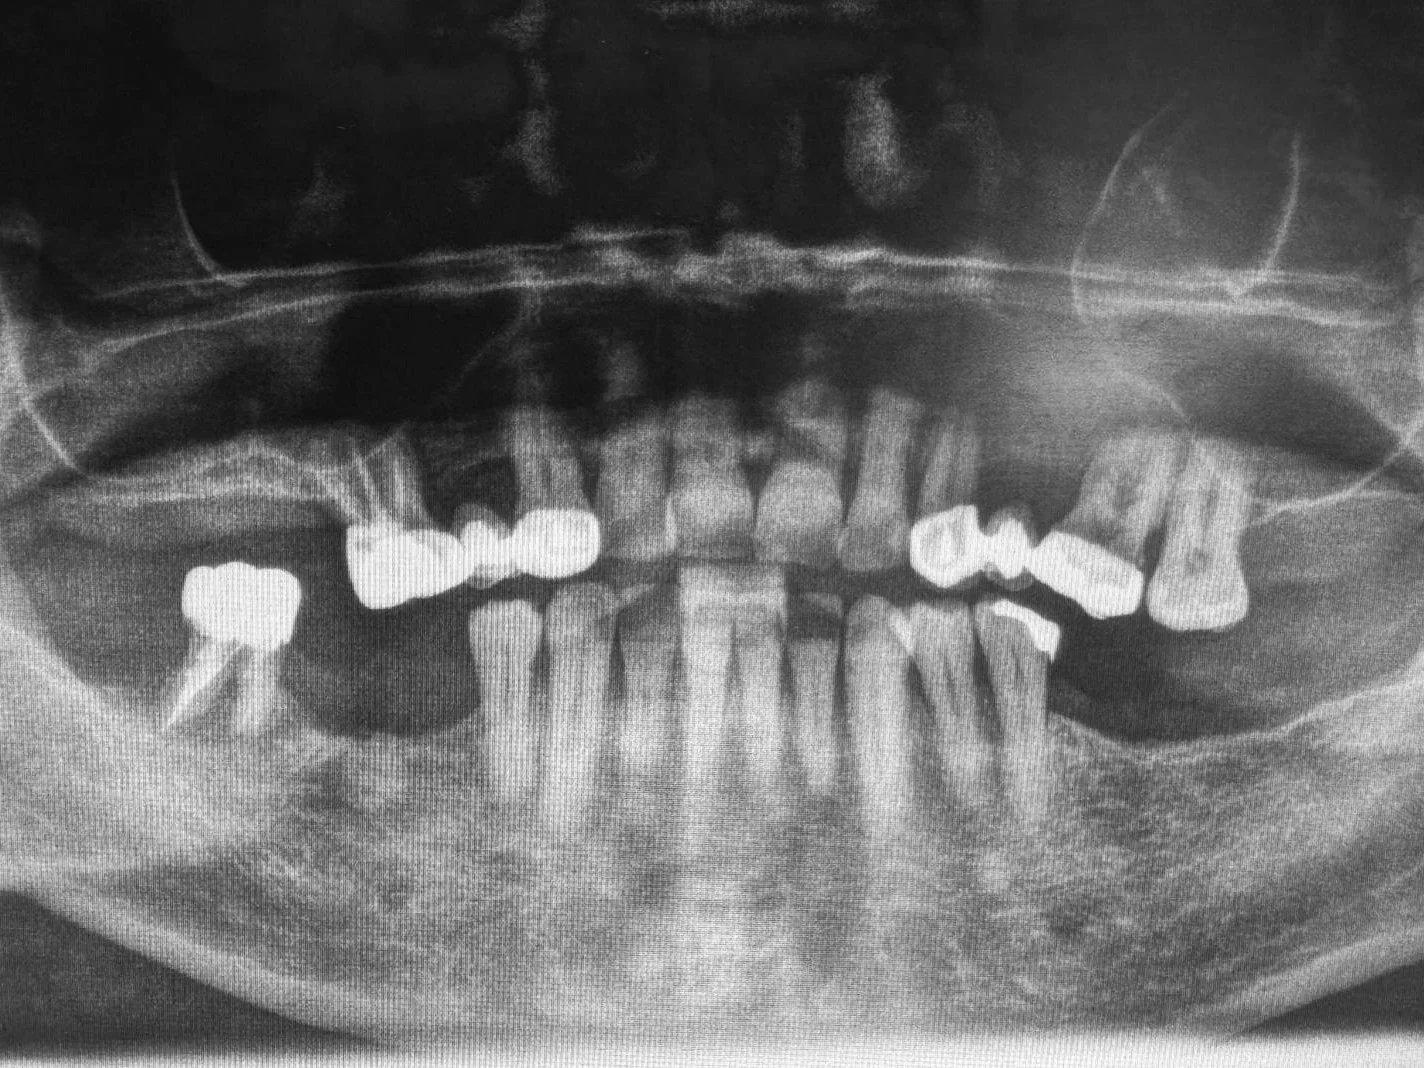

Estrazione e Implantologia

Endodonzia conservativa

Ortodonzia